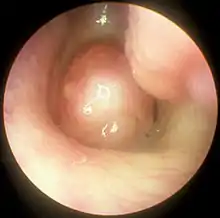

Полип носа

Назальный полип, или полип носа, — полиповидная масса, в основном возникающая из слизистой носа и придаточных пазух. Представляет собой разрастание слизистой, часто сопровождаемое аллергическим ринитом. Этот вид полипа легко перемещается и нечувствителен к прикосновениям (англ. freely movable and nontender).